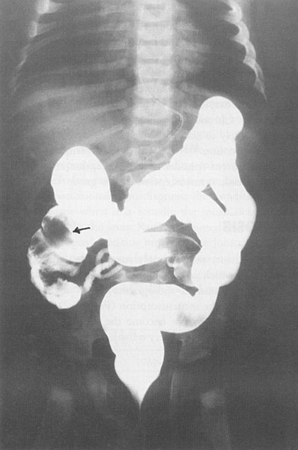

More - upper gastrointestinal series with small bowel follow-through:

oedema and ulceration of the mucosa with luminal narrowing and strictures

More - upper gastrointestinal contrast study:

dilated small intestine; may demonstrate a transition zone of obstruction

More - lower gastrointestinal contrast study: